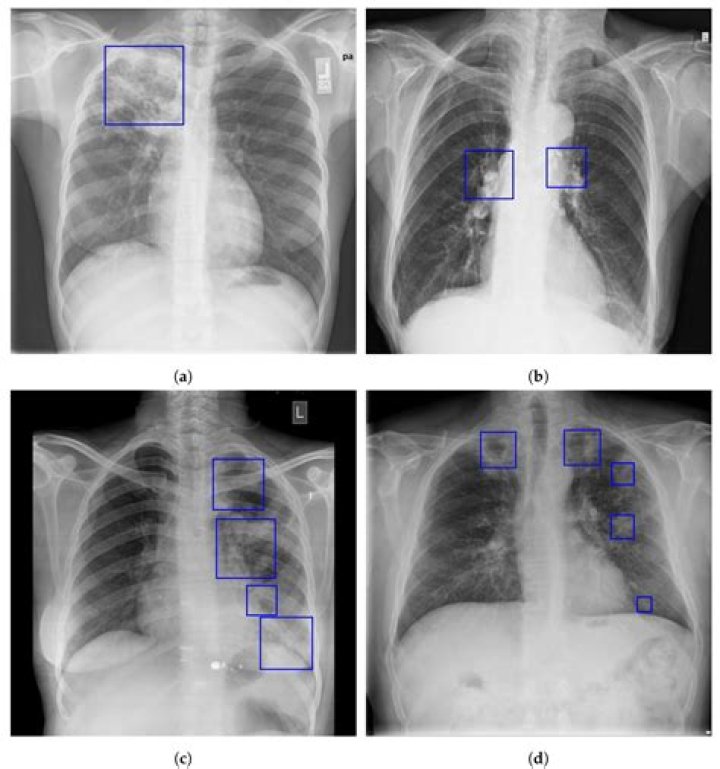

chest X ray has low sensitivity. However, it is used to identify associated problems with GERD like esophagitis, esophageal erosions, and ulcers. Findings in barium swallow imaging include the following: Free acid reflux.